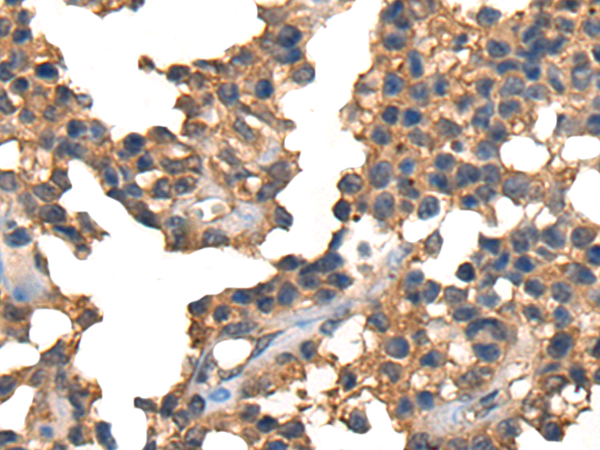

IHC positive control: |

Human liver cancer and Human ovarian cancer |

IHC Recommend dilution: |

25-100 |